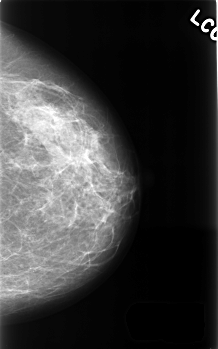

C_0415_1.LEFT_CC

LEFT_CC LINES 4528 PIXELS_PER_LINE 2824 BITS_PER_PIXEL 12 RESOLUTION 50 NON_OVERLAY